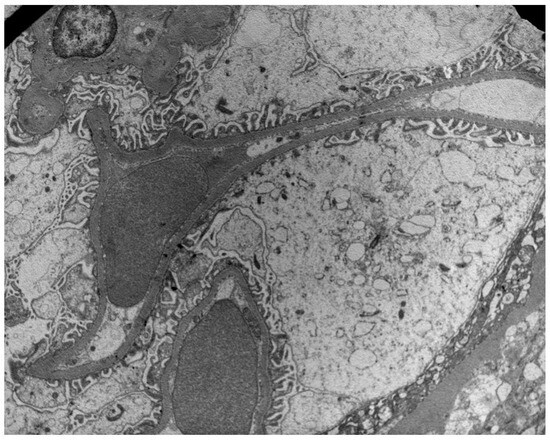

3.2. Electron Microscopy